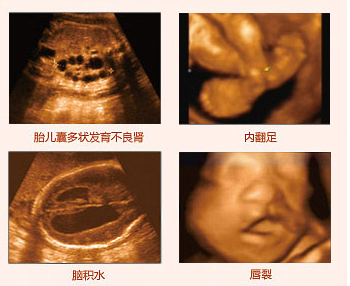

四維彩超排畸圖片

一般而言,四維彩超可篩查以下項目:

(1)生理指標:測定胎兒孕周、分析胎兒生長發(fā)育情況;

(2)胎兒面部畸形:如唇腭裂等;

(3)神經(jīng)系統(tǒng):無腦兒、腦積水、小頭畸形、脊柱裂及腦脊膜膨出;

(4)泌尿系統(tǒng):腎積水、多囊腎及巨膀胱、尿道梗阻;

(5)消化系統(tǒng):臍部腸膨出、內(nèi)臟外翻、腸道閉鎖及巨結(jié)腸等;

(6)其它畸形:短肢畸形,聯(lián)體畸形等;

(7)評價單胎或多胎妊娠/高危、異常妊娠/羊水量有無異常;

(8)進行胎盤定位及檢查有無異常。推選閱讀 四維彩超對肚中寶寶會有影響嗎